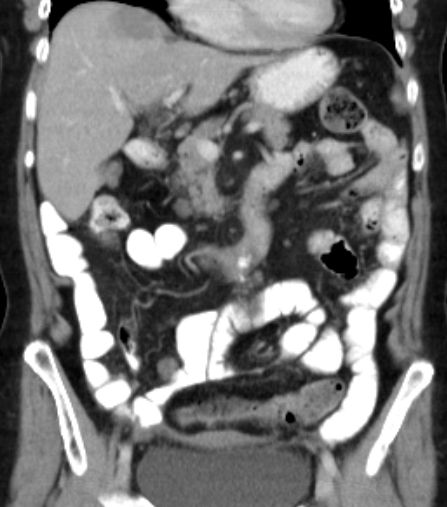

Spätrezidiv 77-jährige Frau bei der vor 13 Jahren ein Ovarialkarzinom behandelt wurde: Hysterektomie, bilaterale Adnexektomie, Omentektomie, Appendektomie, 6 Zyklen Carboplatin/Taxol

Nebendiagnosen: Mammakarzinom links 1977 (Ablatio + Axilladissektion)

Jetzt: peritoneale und Lebermetastasierung, mediastinale Lymphknotenvergrößerung.

Leberpunktion: Adenokarzinom. Die Tumorinfiltrate zeigen angedeutet papillären Strukturmuster. Immunhistologie: CK 7 stark positiv. Nukleär deutlich Östrogen sowie WT1. CK 20, CEA, CDX2, TTF1 negativ.